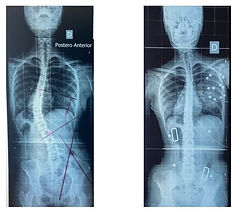

Escoliose

Idiopática